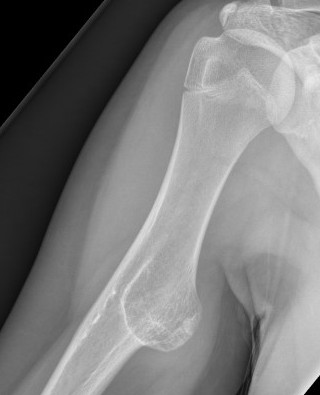

X-ray

Cortical and marrow continuity

Types

1. Pedunculated - has a stalk, points away from joint

2. Sessile - attaches to bone with a broad base

Pedunculated

Protuberant bony lesion arising adjacent to physis

- directed away from joint

- cortical bone and marrow space continuous

Sessile

Proximal humerus

Bae et al J Pediatr Orthop 2014

- 31 patients with proximal humerus osteochondromas

- anterior / lateral / posterolateral debulked 92%

- posteromedial debulked 68%

- recurrence 2/31 (6.5%)